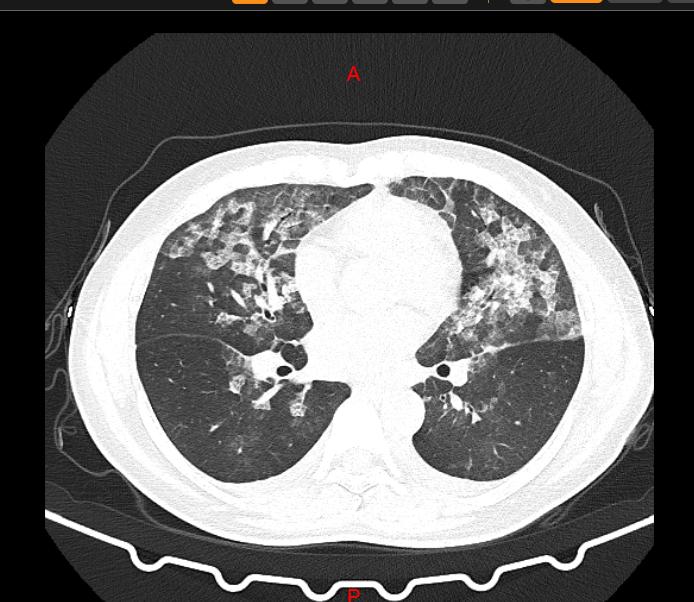

↑↑張女士肺部CT 王女士肺部CT 肺部CT均呈毛玻璃影難道是……新冠病毒? 管床醫(yī)師李鳳芝反復(fù)追問病史,兩位均無流行病學(xué)史,隔離病區(qū)主任張小紅看完患者的影像學(xué)資料及各項檢查結(jié)果后說:“這兩位患者考慮為過敏性肺泡炎,現(xiàn)在我們必須詳細(xì)詢問病史,了解過敏的物質(zhì)! 過敏性肺炎? 原來兩位女士居家期間,因為害怕新冠肺炎,每天定時在家里噴灑84消毒液,而且都是高濃度的! 每次消毒后,張女士和王女士頭暈、乏力的癥狀明顯加重! 過敏性肺泡炎是指易感人群反復(fù)吸入各種具有抗原性的有機粉塵、低分子量化學(xué)物質(zhì),引起的一組彌漫性間質(zhì)性肉芽腫性肺病。反復(fù)發(fā)作可致肺纖維化,甚至可發(fā)展為呼吸衰竭。 慎用84消毒液 慎用84消毒液 84液消毒效果雖然好,卻不能盲目使用,一定要注意它的危害! 當(dāng)不慎接觸到84消毒液時該怎樣做? 皮膚接觸:脫去污染的衣著,用大量流動清水沖洗。 眼睛接觸:提起眼瞼,用流動清水或生理鹽水沖洗,并就醫(yī)。 吸入:迅速脫離現(xiàn)場至空氣新鮮處,保持呼吸道通暢,如呼吸困難,應(yīng)立即并就醫(yī)。